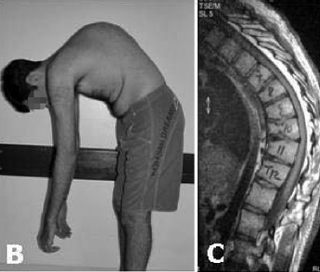

Como a dorso curvo postural difere da Doença de Scheuermann?

O dorso curvo postural é móvel e corrigível com extensão, enquanto a Doença de Scheuermann envolve cifose estrutural rígida e não corrigível com extensão.